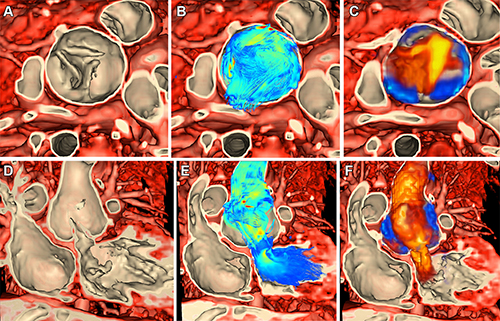

Figure 4. Integrated rendering of myocardial tissue and flow vectors from ferumoxytol-enhanced four-dimensional flow acquisition from cardiac MRI in a 5-year-old female patient with neoaortic insufficiency (patient 4). (A) Surgical view of neoaortic valve in systole. (B) Surgical view of simultaneous rendering of tissue and dense streamlines in systole. (C) Surgical view of simultaneous rendering of tissue and flow with “Doppler-like” rendering encoding velocity relative to annular plane in systole. (D) Coronal view of neoaortic valve in systole. (E) Coronal view of simultaneous rendering of tissue and dense streamlines in systole. (F) Coronal view of simultaneous rendering of tissue and flow with Doppler-like rendering encoding velocity relative to annular plane in systole.